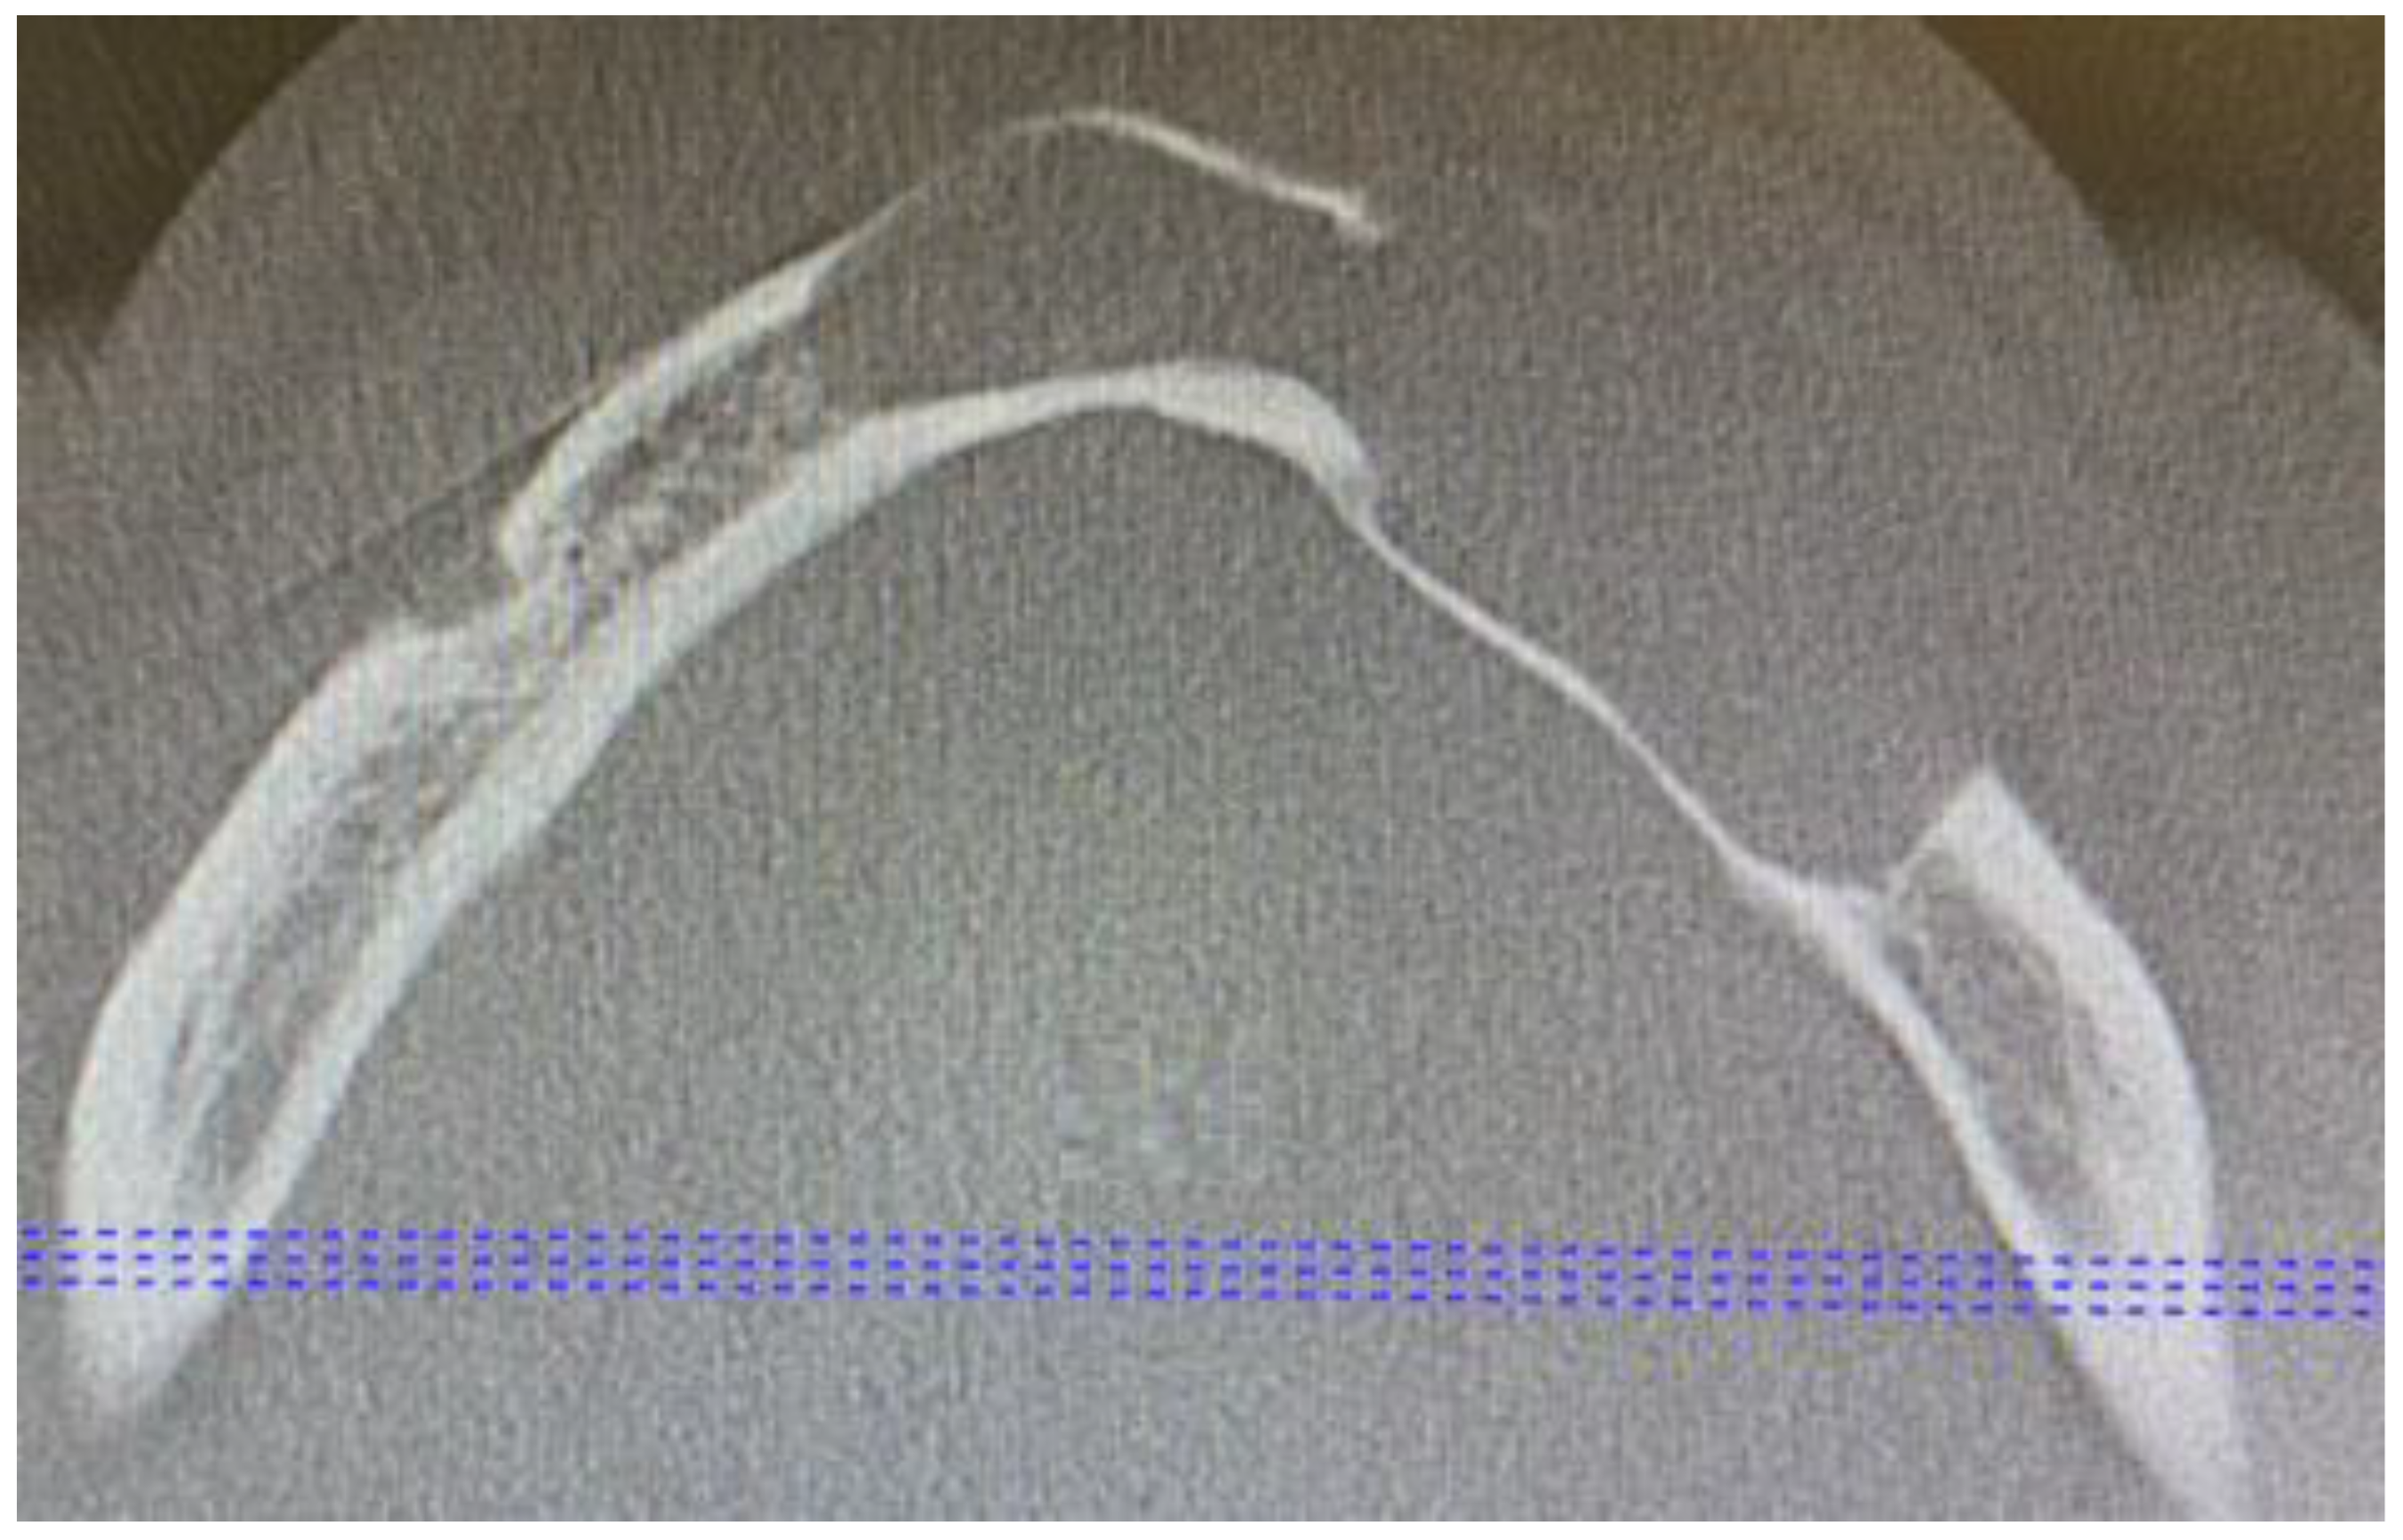

A 62-year-old Caucasian male was referred for consultation because of a cyst in the mandibular anterior and left body area associated with teeth mobility. The lesion was incidentally discovered by a dentist on a routine panoramic radiograph. On imaging, there was a polycystic lesion, quite big in diameter, with well-defined borders, visible inner cystic septa, and displaced 33,34,35 teeth. The cystic cavity ranged from tooth 43 towards 36, causing superior destruction of the alveolar ridge between teeth 33 and 34 and inferiorly spreading closely towards the inferior margin of the mandible. This expansive lesion was radiolucent with some septa with cortical buccal and alveolar ridge expansions (Figure 1).

Figure 3. Axial CBCT scans. A great bone dehiscence in the labial part of the bone is noticeable.